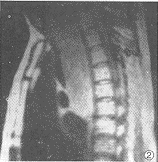

MRI检查: 食管中上段(T7以上)巨大香肠样软组织肿块,约27.0cm×6.5cm×5.2cm,T1 WI呈较均质等信号(图1、2),T2WI呈明显高信号(图3),肿块于主动脉弓附近尤为显著。M RI诊断:食管中上段占位性病变。

图1 横轴位T1WI示食管腔内等 信号软组织肿块,约6.3cm×5.2cm,前缘呈菜花状,气管受压向前推移 图2 矢状位T1WI示食管中上段软组织肿块,呈较均质等信号,边缘较清楚,大小约27.0 cm×6.5cm 图3 与图2相同层面,矢状位T2WI示食管中上段软组织肿 块呈高信号